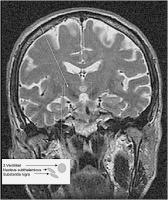

Morbus Parkinson - Nucleus subthalamicus

Abbildung 2: Prächirurgische kernspintomographische Aufnahme des Nucleus subthalamicus. Die Kernspintomographie erlaubt eine sehr gute Visualisierung der Zielstruktur im subthalamischen und pallidalen Bereich. Die geometrische Genauigkeit dieser Untersuchung reicht aber nicht aus, um ausschließlich darauf die Zielpunktberechnung zu basieren. Hierzu werden weitere Untersuchungen, wie Computertomographie und stereotaktisches Röntgen, benötigt.